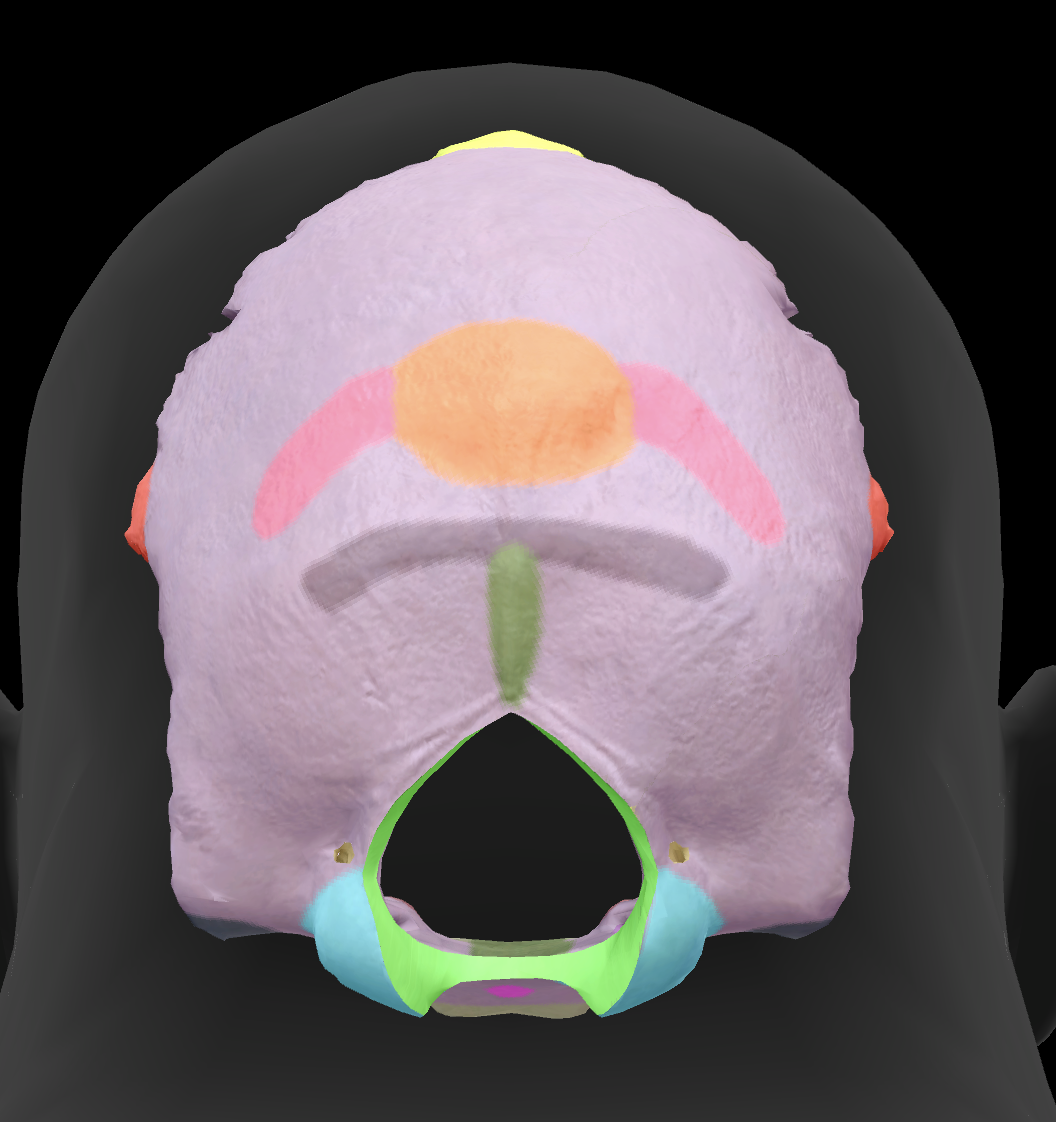

What is the name of this feature?

external occipital protuberance

What is the name of this feature?

superior nuchal line

What is the name of this feature?

inferior nuchal line

What is the hole called?

foramen magnum

What is the name of this feature?

occipital condyles